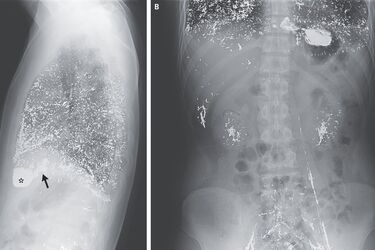

Через це рівень ртуті у його сечі перевищував допустимий у більш ніж 600 разів, а в крові — у 360 разів. Рівень гемоглобіну був у нього вдвічі меншим за нижчу межу норми. На рентгені лікарі помітили численні металеві вкраплення у легенях, печінці, нирках, венах та правому передсерді й шлуночку.